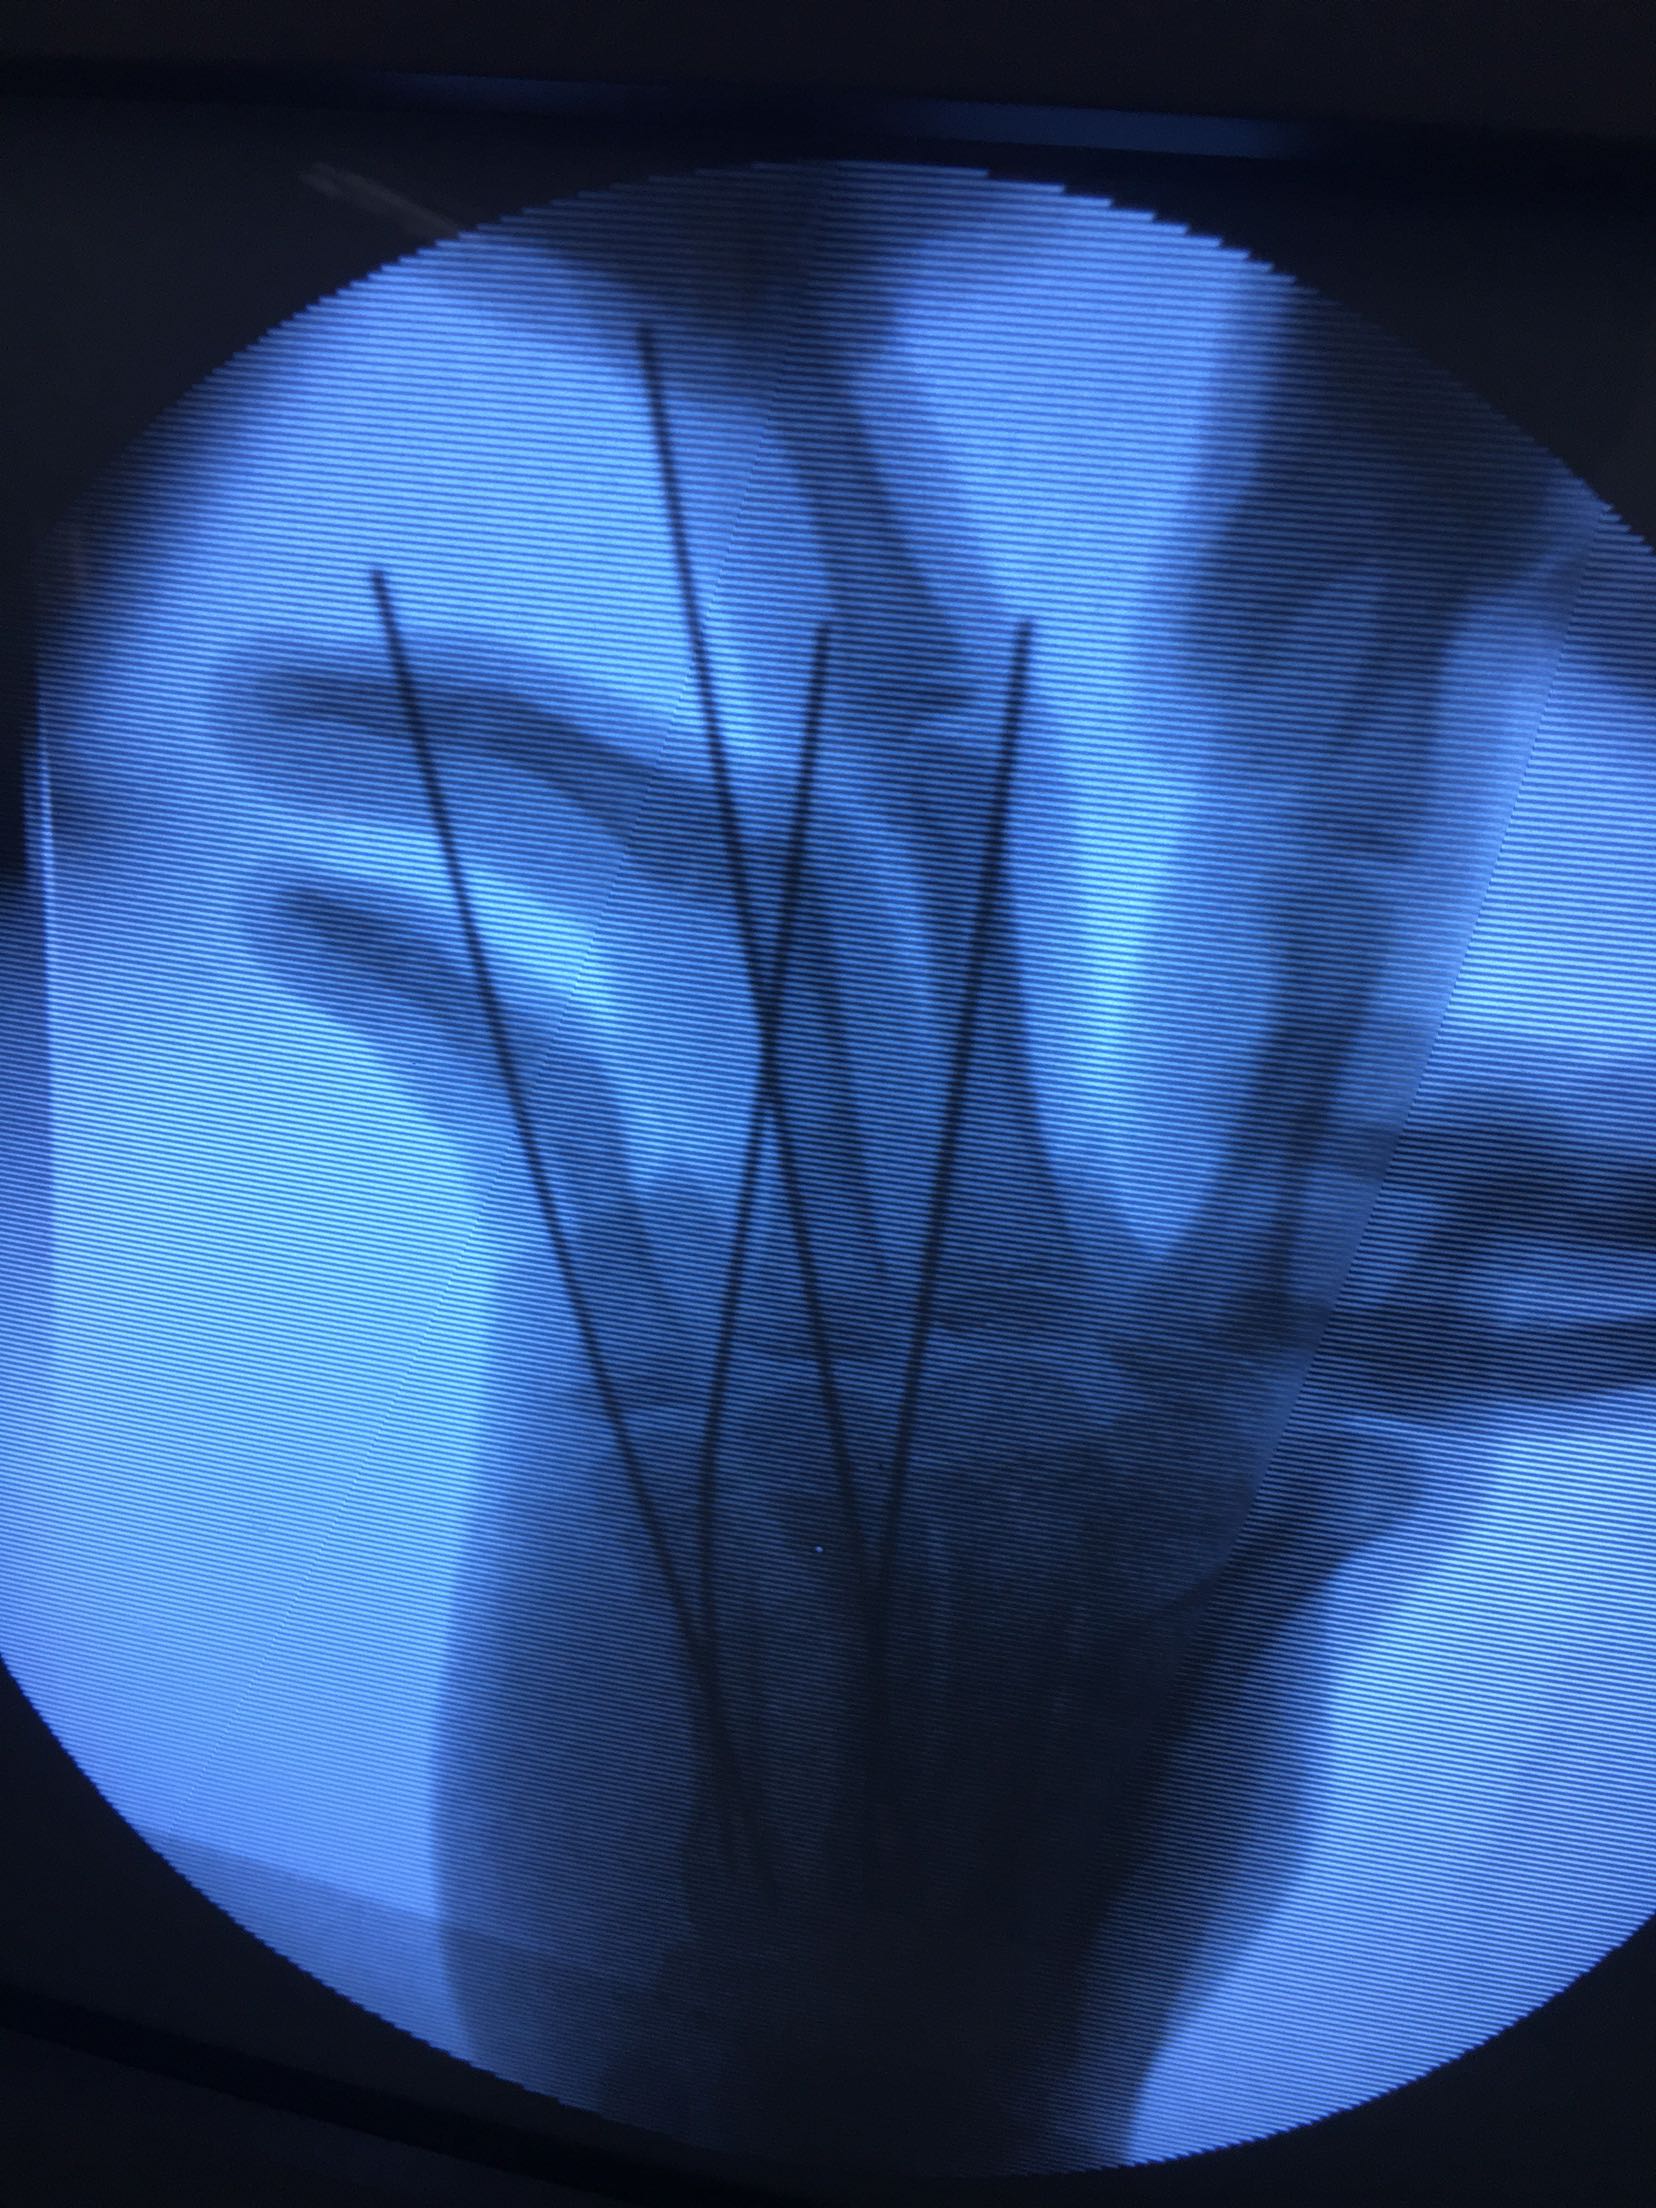

右第四,五掌骨骨折(微创)

完善检查,在臂丛麻醉下行闭合复位内固定术,术后抗炎,消肿止痛等对症处理,右手石膏托制动。